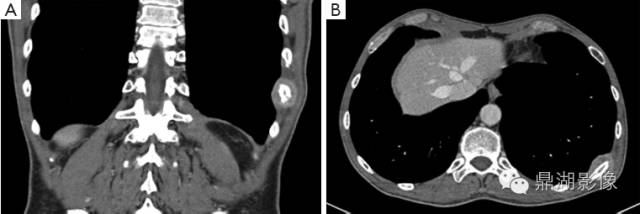

(十)神经母细胞瘤骨转移 神经母细胞瘤又称成神经细胞瘤、交感神经细胞瘤、交感神经母细胞瘤。肾上腺髓质肿瘤多系次类,此病为儿童,尤其是幼儿较常见的恶性肿瘤。发生率为3.4%~18.1%,可分胸型和腹型,65.5%发生于腹部,临床表现有三大表现,上腹部凸凹不平,坚硬且固定,常伴有腹痛的包块;全身情况迅速恶化;早期骨转移。早期骨转移为本病的重要特点之一。

神经母细胞瘤骨转移

1. 颅骨 呈溶骨性及成骨性表现,或混合表现。溶骨性改变常位于颅缝附近,呈虫蚀样破坏或骨质增生。颅骨转移的特征性表现为沿颅缝对称性分布的破坏及颅为板放射状骨针。颅骨病变周围有软组织肿块。骨盆、肩胛骨、下颌骨等扁骨X线片表现基本同颅骨。

2. 脊柱 神经母细胞瘤也常侵犯脊柱,特别是所谓的哑铃状肿瘤可侵蚀破坏椎体,椎体呈现大小不等的溶骨性改变,压缩变扁,边缘毛糙不齐且模糊。有时也显示骨质增生,椎体前后缘凹陷。

3. 长骨 以侵犯股骨较常见。病变常位于长骨干骺端,早期表现为干骺端骨松质,骨小梁毛糙、模糊、不整齐,进一步发展则出现筛孔状、斑点状小透亮区,周围轻度骨质增生。病变常对称性分布,有时出现对称性骨质缺损及层状骨膜反应。

神经母细胞瘤广泛的骨损害应注意与白血病,尤文肉瘤及急性骨髓炎相鉴别。